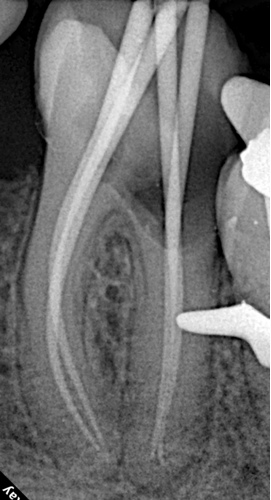

2️⃣ Working Length Determination

Working lengths were precisely measured using the ROGIN Apex_S electronic apex locator.

- Mesial canals: 27mm

- Distal canal: 25.5mm

Accurate length determination was critical in this extreme-length case to avoid over-instrumentation or missing the apical terminus.